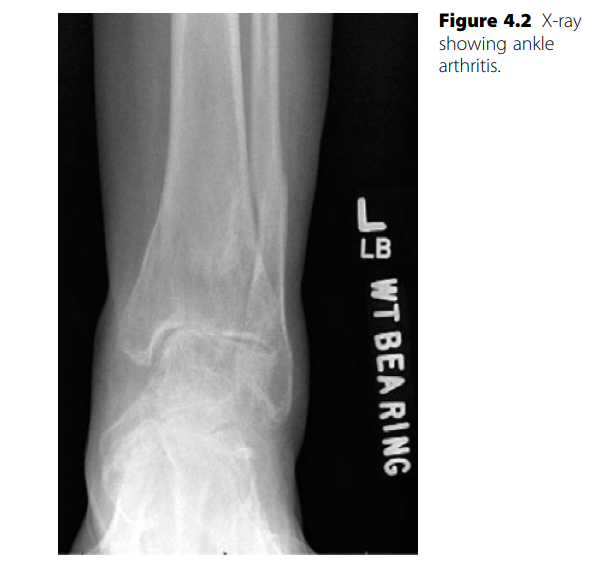

Foot and ankle structured oral questions2: Ankle arthritis EXAMINER : Describe the findings on this X-ray. ( …